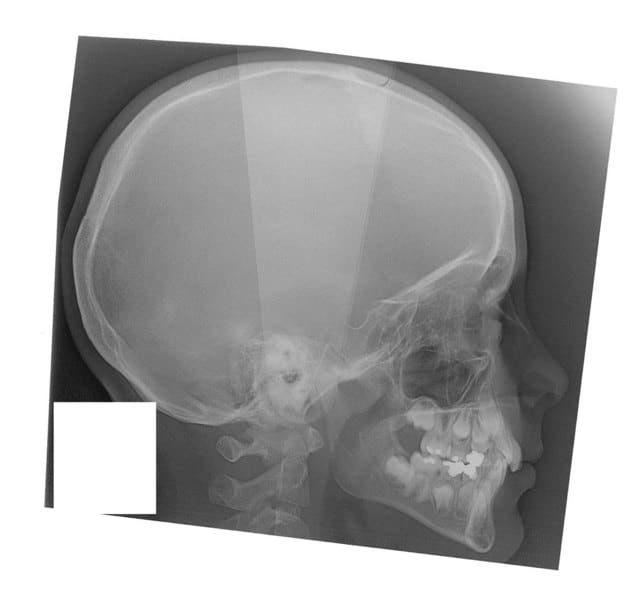

22/05/2008 à 00h10

début 2008,quadhélix en 0.28,pour vestibuler la 2,ce qui est fait

Tele2002 qhiepn - Eugenol

Tele2007 b6yul0 - Eugenol

et les profils

Profil2007 dxpeqm - Eugenol